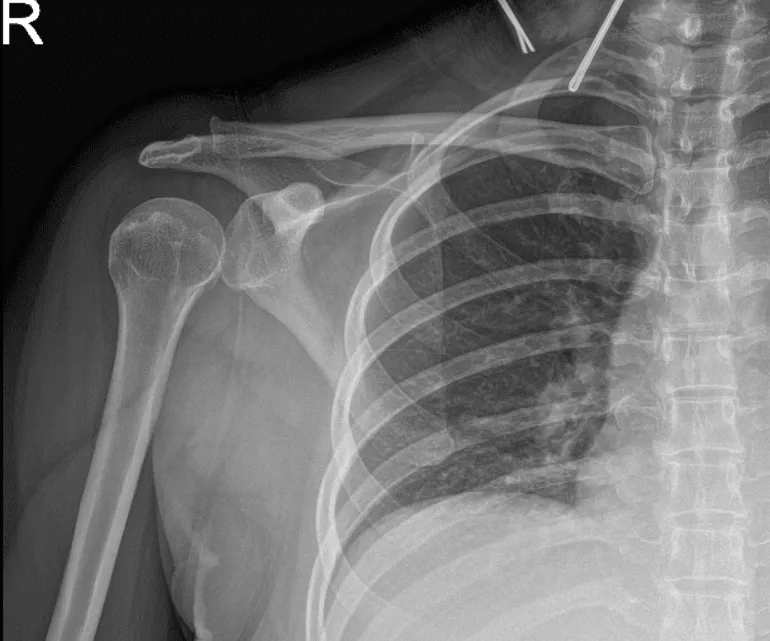

El paciente también presentó los resultados de una radiografía y mostró radiografías normales del hombro derecho.

Radiografía del hombro derecho